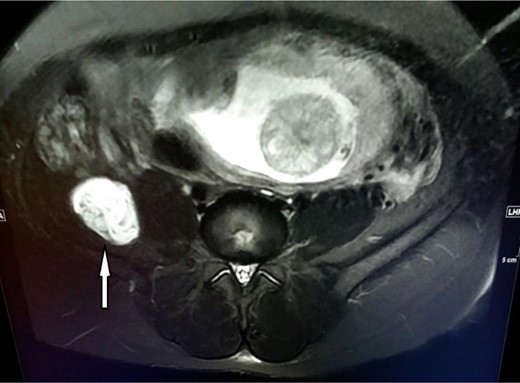

Because of the persistant pain of the patient, she was suggested to have surgery. The patient, lying in the left lateral decubitus position, incised on the mc burney point and the preperitoneal area was reached. This area was dissected towards posterolaterally and retroperitoneum was reached. The cyst was dissected from the adjecent tissues and the iliacus muscle. Posteriorly, the cystic mass was densely adhered to nervus cuteneus femoris lateralis (Fig. 2). It was separated from the nerve by sharp dissections and sent to a histopathological examination (Fig. 3). Histopathologically, it was confirmed that the mass was hydatic cyst. Albendazol treatment was not given to the patient who had not any complaints in postoperative follow-ups. She gave birth at 41th week and there was not recurrence in her 4 years follow-up.

Cystic mass densely adhered to lateral femoral cutaneous nerve; before dissection.